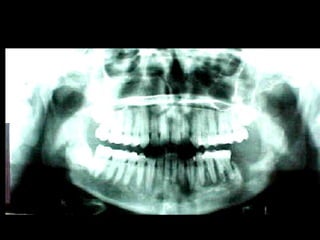

En el estudio radiográfico determinamos que el factor causal fué un foco séptico

dentario a nivel de segundo molar inferior izquierdo.